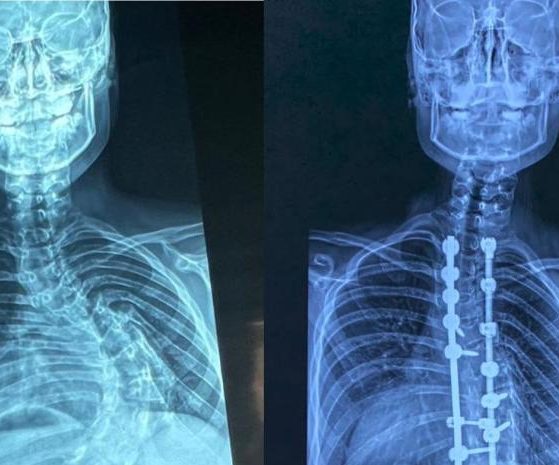

La escoliosis consiste en una desviación de la columna vertebral superior a 15 grados.

En el país se han efectuado más de 350 intervenciones quirúrgicas para corregir deformidades en la columna de pacientes pediátricos